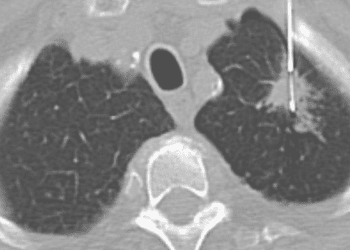

Image: PD